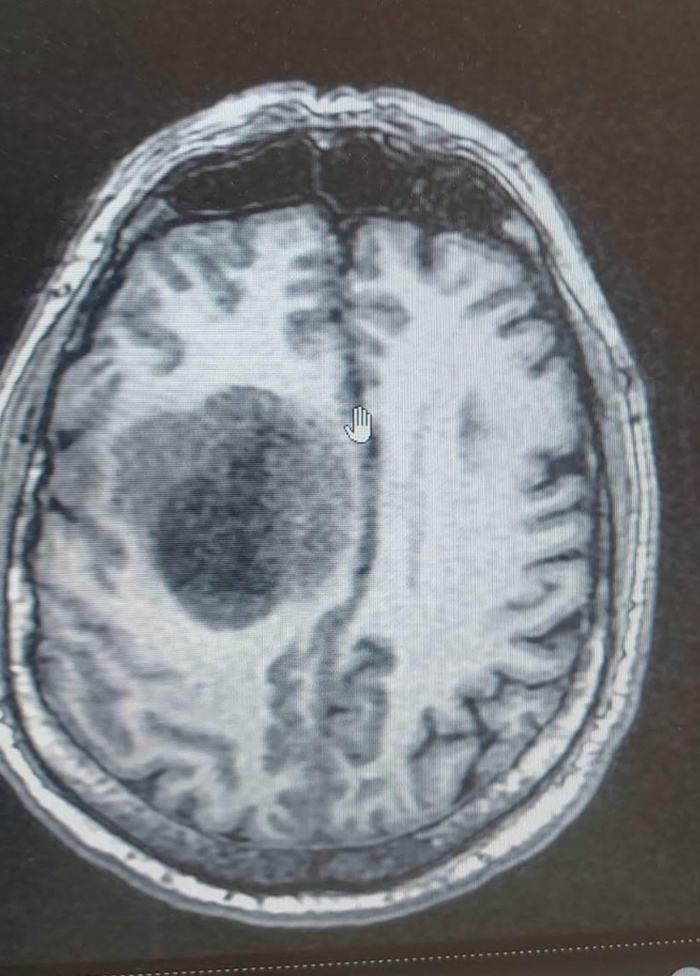

Ответ Harmstring в «Думали мигрень, а это…»17

Отвечу тоже постом. Бывает даже и без Эпи приступов. Отец всегда был весёлым, активным, общительным человеком. А тут стали замечать, что "подвисает", будто не тут он, где-то в себе. Не такой болтливый. Мы с ним часами могли по телефону разговаривать, а тут звонит раз в день просто узнать как дела, только по делу, без болтовни. Думали может стареет, энцефалопатия. Где-то в июле- августе это началось. Когда потом врач его спрашивал про жалобы, отвечал: "жена сказала, что я изменился", то есть он не замечал ничего. Осенью за рулём на встречку его начало тащить. Потом вообще левая рука слушаться перестала. После того, как упал несколько раз за день, повезли в больницу. Там МРТ с контрастом: глиома IV, 5 на 5 см. Состояние буквально за два дня ухудшилось до такой степени, что перестал вставать (но сам он был в полной уверенности, что встаёт и ходит, видимо, мозг отказывался осознавать беспомощность тела). Причём, МРТ всего, и головы тоже, делали за полгода до этого. То есть болезнь развилась за считанные месяцы. Потом операция, химия, восстановление как после инсульта. Но прогнозы по этой болячке не слишком оптимистичные, он статистику не нарушил, к сожалению.

Вообще ничего не болело, больше никаких симптомов не было. Прислушивайтесь к себе и к близким. Иногда если что-то кажется, оно не кажется

Я потеряла папу 6 сентября. Ему было 67. Не намного старше вашего. Я очень сильно вас понимаю. Он был мои другом, опорой, советчиком, помощником. Очень любил внуков, помогал с ними, водил на занятия, когда были маленькими, а я работала.

В апреле прошлого года заметила у него родинку, она мне не понравилась, отправила к онкологу. По итогу в мае вырезали меланому, 1А, вовремя "поймали", без метастаз и последующего лечения. Сделали МРТ почти всего организма: всё хорошо. Уже потом начали вспоминать, что с конца лета он стал не такой как обычно. Он всегда был балагур, душа компании, рассказывал истории, анекдоты. А тут на днях рождения родных в августе всё больше молчал. Осенью съездили в Египет, потом в ноябре поехали с мамой а Сочи в санаторий. Он ни разу не был до этого на Чёрном море. В санатории стало хуже, падал с кровати, проблемы с координацией и какая-то заторможенность. Сделали КТ, подозревали инсульт. В выписке: данных за инсульт нет, срединные структуры смещены на 1,5 см. И ничего у врачей даже не дернулось с такими данными. Должны были из Сочи 1 декабря лететь домой, но взяли билеты на неделю раньше- 24 ноября (и санаторий отстой, и состояние ухудшалось). В аэропорт заходил сам, из самолёта уже на коляске везли, левая сторона не работает. 27.11 положили в больницу, когда с кровати не смог встать. По МРТ опухоль головного мозга 5*5*3 см объемом 35 мл с прорастанием в мозолистое тело. 29.11 прооперировали, врач сказал, что на день-два позже и смысла оперировать уже не было бы. Диагноз был как гром среди ясного неба. Понимание, что это всё. Врачи давали 2-3 месяца. Он 4 месяца пролежал. В марте встал на ноги, хорошо себя чувствовал. Каждые 28 дней химия. На её фоне вроде не было роста опухоли. Но начались приступы эпилептические. Сначала иногда, потом чаще. Летом они с мамой жили на даче, ездили за грибами, гуляли. В конце августа был мой ДР, я пригласила семью в кафе. Он на следующий день мне написал: "хорошо посидели". Я ответила: "хорошо, что все пришли". 4 сентября был последний приём химии. Ему стало хуже, приступы были всё чаще и сильнее, начали противоэпилептические препараты. 5 числа заходила к нему, он жаловался, что очень плохо себя чувствует, слабость и вообще... 6 числа звонит мама с работы: "не могу дозвониться до папы, сходи к нему, проверь" (я работаю рядышком). Пришла, а он лежит в ванной. Поняла, что всё. Он был ещё теплый. Видимо, опять приступ случился. Или сердце. Мы вскрытие не делали: какая разница, что конкретно добило? На похоронах у меня было полное ощущение нереальности происходящего, что это не правда, не может быть так. Как теперь без него? Очень долго одёргивала себя, когда хотела ему отправить что-нибудь смешное или интересное. До сих пор, видя что-то смешное, ловлю себя на мыслях: "папе бы понравилось". Про себя постоянно разговариваю с ним, рассказываю, как дела у нас. Хоть понимание, что с таким диагнозом долго не живут, было с декабря (выживаемость 1,5 года с глиомой 4 составляет около 10%, а у него, к тому же, был дикий тип, который плохо реагирует на лечение), но всё равно казалось, что всё наладилось, всё хорошо. Ждали, конечно. Но не ожидали. Не сейчас. Очень вам соболезную.